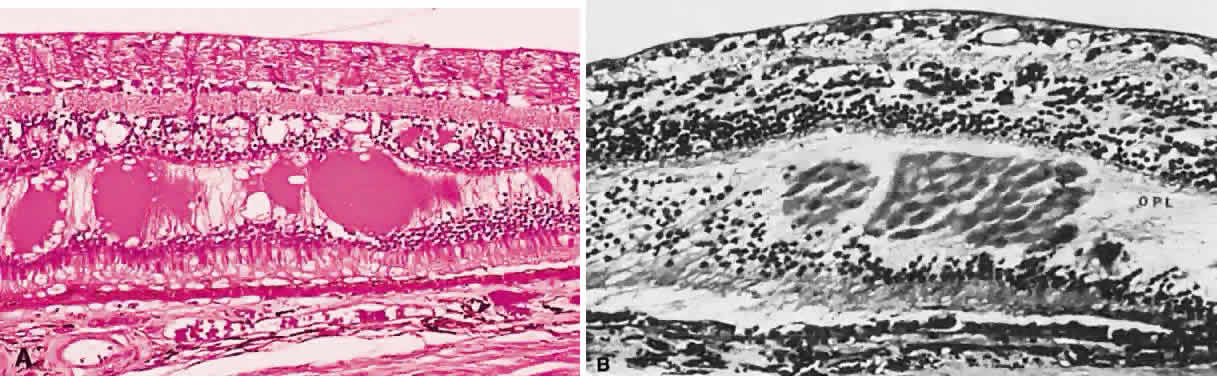

Typical cystoid degeneration involves the formation of cyst-like spaces at the level of the outer plexiform layer (Blessig-Iwanoff cysts) (Fig. 59). These are common lesions, present in most persons from the first decade of life. These “cysts” appear to become more numerous with age. Coalescence of these cysts may result in “senile” retinoschisis.23 Reticular cystoid degeneration involves a disruption at the level of the nerve fiber layer. It is located frequently just posterior to the area of typical cystoid degeneration. A network of fine, branching blood vessels is seen commonly over the surface of reticular cystoid degeneration.

Fig. 59. A. Typical cystoid degeneration of the peripheral retina with cyst-like spaces in the outer plexiform layer (Blessig-Iwanoff cysts). These cysts sometimes coalesce, and the inner layer breaks down to form a hole. B. Peripheral cystoid degeneration with atrophic holes. (A, courtesy of Ralph C. Eagle Jr, MD, Philadelphia, PA. B, courtesy of William Tasman, MD, Philadelphia, PA).

Degenerative or senile retinoschisis involves a splitting of the retina at the level of the outer plexiform layer for a distance of at least one disc diameter. As seen ophthalmoscopically, degenerative retinoschisis frequently has a “beaten metal” appearance, and fine, white dots may be seen within the cavity. These dots are thought to represent columns of Müller cells that have been stretched to the point of rupture: the clinically observed dots are Müller cell remnants that remain adherent to the internal limiting membrane. These Müller columns are believed to be responsible for the unevenness of the outer schisis surface; the inner surface is typically smooth. Large holes in the outer wall of the schisis cavity (by convention, “outer” refers to the scleral side of a retinal lesion whereas “inner” refers to the vitreous side of the retina) are frequently observed (Fig. 60), although smaller inner layer holes are less common. The presence of holes in both the inner and outer walls of a schisis cavity creates a pathway from the vitreous to the subretinal space, and a rhegmatogenous retinal detachment may develop.

Fig. 60. A. Photomicrograph of a retinoschisis cavity with a hole in the outer layer (OL). The inner layer (IL) is intact. Typical peripheral cystoid degeneration is present (arrow). B. Outer wall holes in a patient with senile retinoschisis. Notice the pocked marked appearance of the outer wall layer peripheral to the holes. (B, courtesy of William Benson, Philadelphia, PA, Wills Eye Atlas of Ophthalmology. Lippincott-Raven Fig 4-58, 1996)